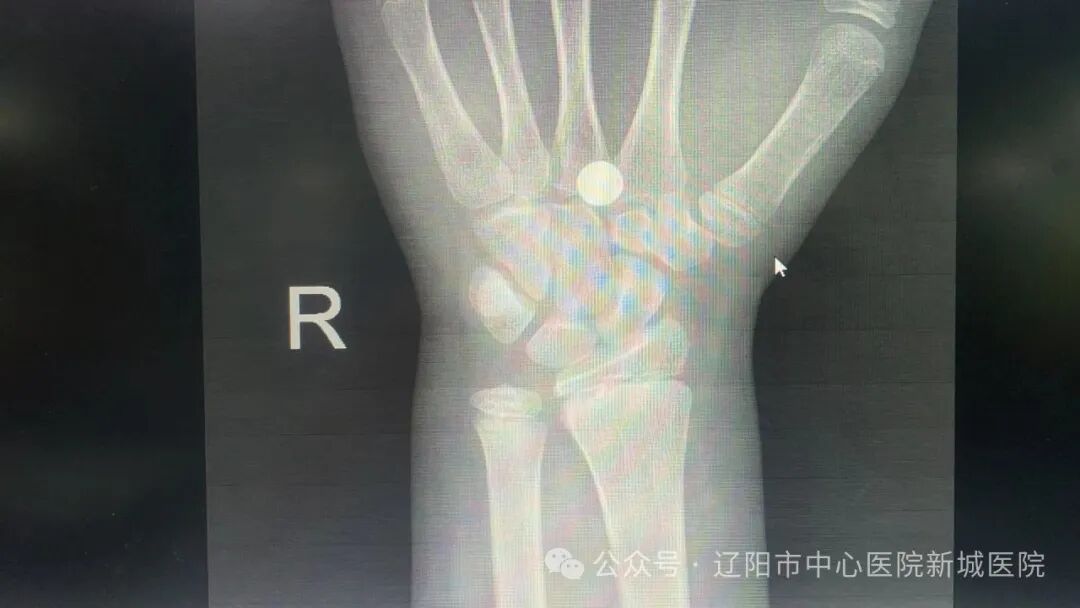

男孩小明在學(xué)校不小心被鐵釘扎到了手掌根部,家長(zhǎng)急急忙忙帶孩子來(lái)到新城醫(yī)院。急診科醫(yī)生快速為孩子檢查傷情,并開具檢查單,醫(yī)院愛心志愿者立即協(xié)助家屬繳費(fèi)后,通過(guò)急診綠色通道進(jìn)入影像中心DR檢查室進(jìn)行拍片檢查。影像中心主任迅速審核檢查報(bào)告;急診科醫(yī)生確認(rèn)男孩的手掌鐵釘未傷及骨骼后,為小明小心翼翼的取出鐵釘、處理鐵釘傷口、仔細(xì)包扎;愛心志愿者幫助家長(zhǎng)領(lǐng)取破傷風(fēng)藥物,醫(yī)護(hù)人員為小明注射破傷風(fēng)針,救治全程不足20分鐘。